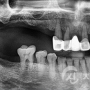

임플란트 치료사례